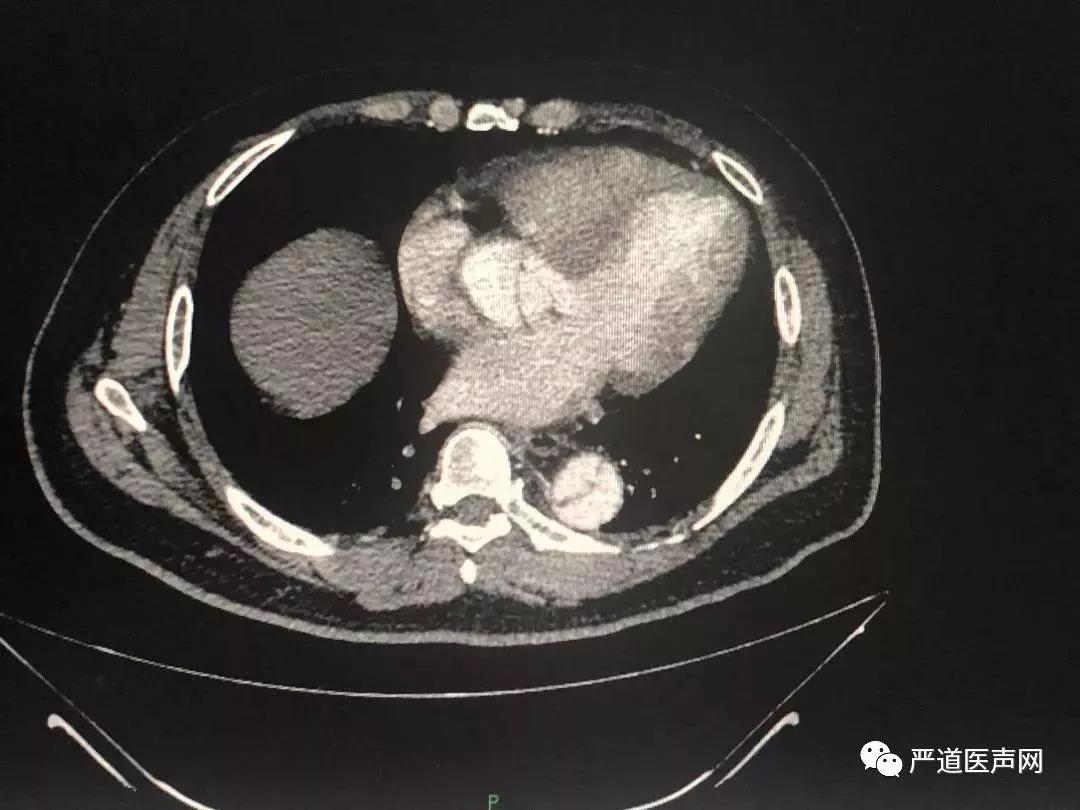

考虑到主动脉夹层可能,经猪尾导管行主动脉造影不安全,接下来完成了主动脉CTA检查:

▲主动脉CT提示:自升主动脉根部开始至腹主动脉分出髂动脉之前全段夹层形成

至此,患者胸背痛的原因基本明确:1型主动脉夹层